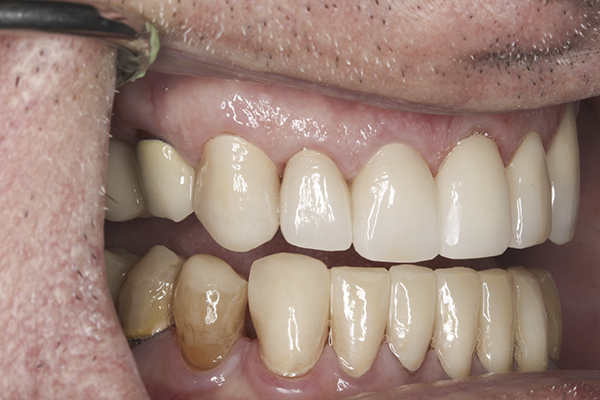

(27.) Provisionals, anterior, close-up view.

Figure 27

(28.) Provisionals, left anterior, close-up view.

Figure 28